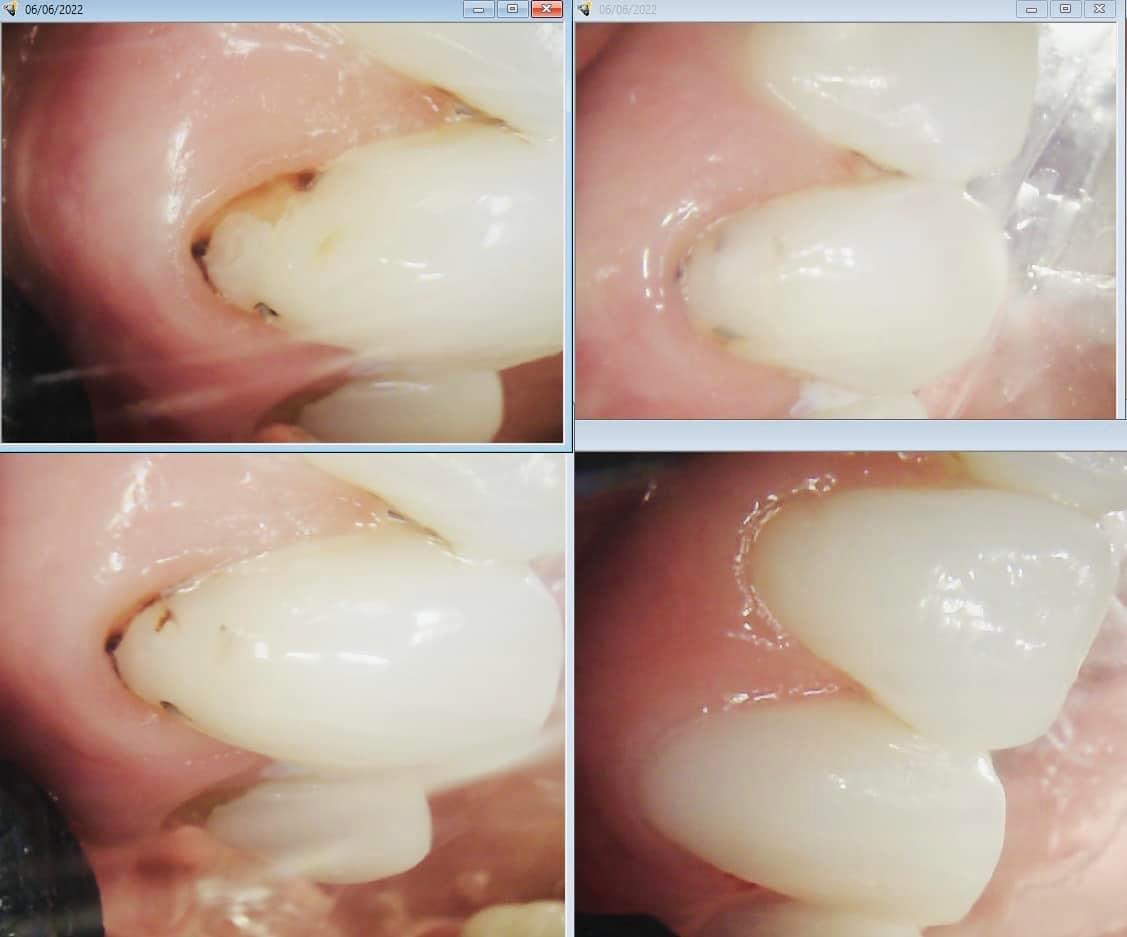

By using advanced techniques to detect cavities early, we help patients protect their teeth before problems become painful or expensive.

With thousands of hours of extra CE courses since completing school Doctor TingTing has taken dentistry to the next level with advanced clinical techniques and diagnosis tools most dentists have never even heard of.

Techniques you won't experience at your average dentist